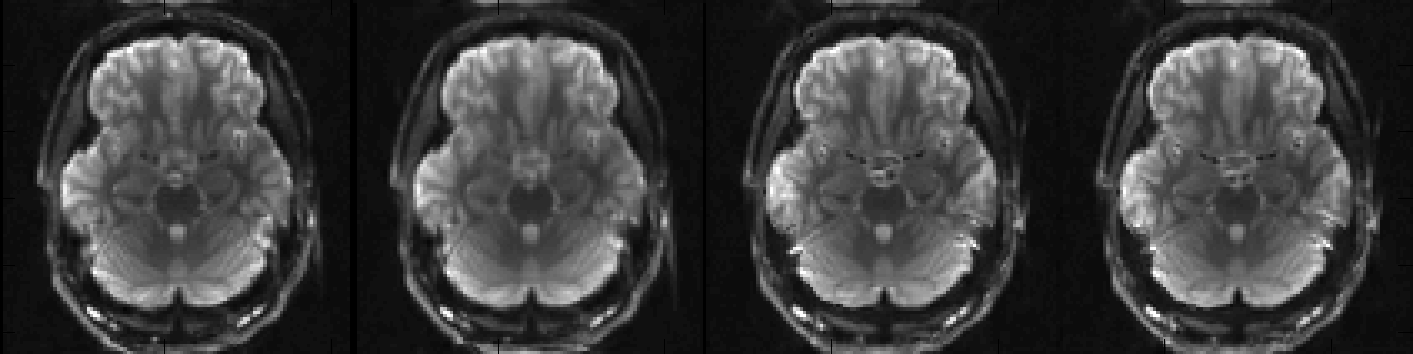

So, let us first take a look at my_unwarped_images.nii.gz to see if topup has done a decent job at correcting the distortions.

I think we can agree that that looks quite good and that we have no reason to think that topup ran into any problems. Let us now look at my_topup_results_movpar.txt to see if we were right in our suspicion that there had been some movement.